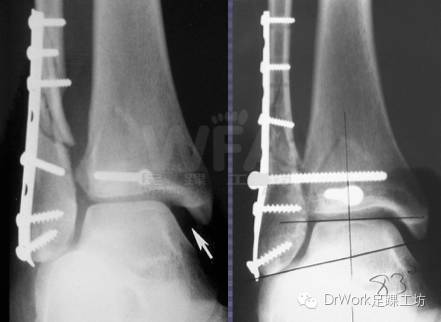

复位后与健侧对比可显著提高复位准确率

• 健侧

• 患侧